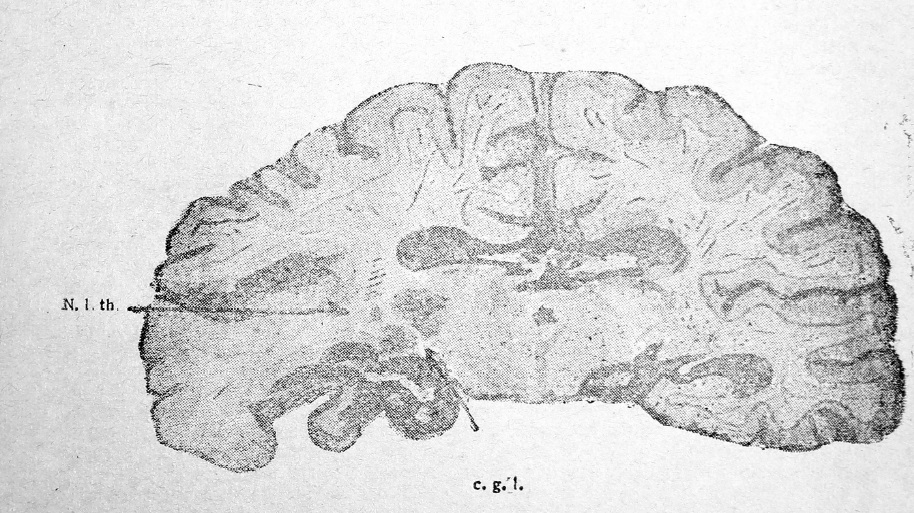

Мы имели случай наблюдать тромбоз а. basilaris, сопровождавшийся размягчением целого ряда областей в бассейне ее васкуляризации. Помимо того, что при аутопсии было установлено размягчение всего стволового отдела, начиная от ножек мозга, включая мост и отчасти полушария мозжечка, оказалось, что ряд очагов имеется и в левой гемисфере. В сосудах основания головного мозга была обнаружена любопытная деталь, обусловившая особую локализацию размягчения в полушарии: а. communicans s. была резко утончена, диаметром конского волоса, имея вид толстой нити равномерного калибра. Правая а. communicans оказалась довольно широкой. Это обстоятельство при условии закрытия тромбом, в результате склеротического процесса b. art. basilaris, позволило восстановить до некоторой степени нарушение кровоснабжения лишь в бассейне правой задней мозговой артерии за счет а. carotis int через а. communicans d. Левая же задняя мозговая артерия не получала кровь ни из а. basilaris, ни из а. carotis int., вследствие непроходимости коммуникаций. Нижеприводимый рисунок 2 иллюстрирует картину размягчения, возникшую в этом случае и в точности совпадающую со схемой Фуа и Николеско, приводимую ими в их руководстве.

На фронтальном срезе, на уровне верхних отделов ножек мозга, имеется большой очаг размягчения в области gyrus lingualis sin. и отчасти gyr. fusiformis et hyppocampi. Имеется красное размягчение в области corp. geniculat. ext., и другое — треугольной формы, обращенное основанием кверху, вершиной книзу, красного цвета, в области наружного ядра левого зрительного бугра. Два последних очага точно соответствуют территории распространения а. thalamogeniculatae. Клиническая картина поражений в этой области может быть иллюстрирована следующими случаями из нашей клиники.

Рис. 2.